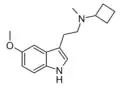

| MiPT | artificial | H | CH3 | CH(CH3)2 | N-Methyl-N-isopropyltryptamine | 96096-52-5 |